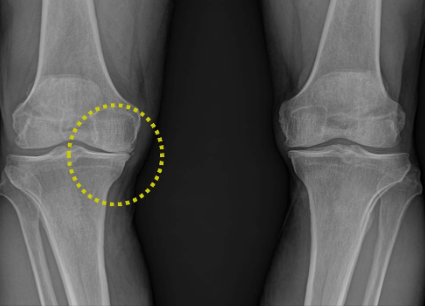

연골의 필수 성분인 글루코사민은 우리 몸에서 원래 스스로 생성되는 성분입니다. 그러나 나이가 들어 가면서 글루코사민 생성 능력은 현저히 감소하게 됩니다. 이에 따라 자연스럽게 관절연골의 완충 능력은 나빠지게 되고, 손상받기 쉬운 상태가 되어 버립니다. 그리고 이 손상이 염증을 유발합니다. 이것이 바로 관절염입니다.